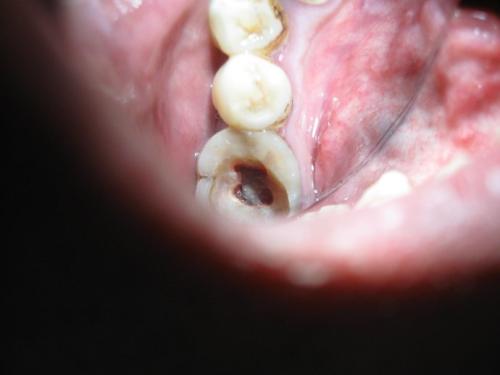

1、牙髓炎的症状主要包括以下几点1 夜间痛 患者在夜间平卧时,由于注意力集中和体位变化,会感觉疼痛更加明显2 疼痛难以定位 患者通常无法准确指出是哪颗牙齿疼痛,且疼痛可能会放射到同侧的太阳穴周围,造成定位困难3 冷热刺激疼痛加重 牙齿在受到过冷或过热的刺激时,疼痛会显著加剧4;可复性牙髓炎的临床表现主要包括以下两个方面1 自觉症状 患者在受到温度刺激,尤其是冷热刺激后,会产生短暂而尖锐的疼痛 当刺激去除后,这种疼痛会很快消失,或仅延续几秒钟的时间,这种情况被称为一过性疼痛2 临床检查症状 检查时会发现牙齿存在近髓龋病或非龋性损害,如冠折导致的牙体缺损等 在去除深龋的龋坏组织后,若未;1 临床症状表现 急性牙髓炎症状典型,多伴有自发痛阵发痛的剧烈疼痛,疼痛有冷热加剧的特点,夜间较白天明显疼痛大多不能定位,呈放散性牵涉性,有时放射到同侧对颌牙耳颞部,多伴有同侧头痛耳痛 慢性牙髓炎临床表现不明显,表现为阵发性疼痛或定时钝痛,病史较长,牙齿有长时间;儿童牙髓炎的症状主要包括以下几点1 牙齿检查和探诊症状 检查患牙时,可发现接近髓腔的深龋或其他牙体硬组织疾患,有时也可见于牙冠有充填体存在 探诊时,常可引起疼痛,有时可探及穿髓孔 牙髓炎症早期,患牙对叩诊无不适反应晚期炎症时,可出现垂直方向叩诊不适2 疼痛表现 由于儿。

3、牙髓病最常见的症状主要包括以下几点1 疼痛 急性牙髓炎疼痛剧烈,夜间性疼痛阵发性疼痛自发性疼痛,且疼痛不定位,常呈放射状 慢性牙髓炎疼痛相对较轻,可能表现为钝疼,冷热水或食物嵌塞到龋洞里刺激牙神经时会引发疼痛,或凉热水敏感2 牙周状况异常 牙周袋相对较深,牙齿较松动;牙髓炎的早期症状可能并不明显,患者可能只是偶尔感到牙齿有隐痛或钝痛随着病情的发展,患者可能会出现长期的冷热刺激痛患牙在咬合时可能会感到不适,或者出现轻度的叩痛大多数患者能够明确指出是哪颗牙齿出现了问题慢性闭锁型牙髓炎的患者通常没有明显的自发痛,但会有长期的冷热刺激痛史。

4、牙髓炎的临床表现主要分为急性牙髓炎和慢性牙髓炎两大类急性牙髓炎的主要症状 剧烈疼痛患者会突然发生剧烈疼痛,疼痛具有阵发性发作或阵发性加重的特点 夜间痛患者常因牙痛难以入睡,或从睡眠中痛醒 温度刺激痛进食冷热食品时,温度刺激会加剧疼痛,患者往往不敢用凉水刷牙晚期表现为“热;牙髓炎症最严重的表现主要有以下几点自发性阵发性疼痛牙髓炎会导致牙齿自发疼痛,且疼痛呈阵发性,即疼痛持续一段时间后会有所缓解,但隔一段时间后又会开始疼痛随着炎症的加重,疼痛的缓解时间会越来越短,而疼痛持续的时间会越来越长夜间疼痛加剧牙髓炎的患者在夜间疼痛症状通常比白天更为;牙髓炎的症状主要包括以下几点1 冷热刺激引起的牙痛 慢性牙髓炎表现为冷热刺激引起的不适感,疼痛相对较轻 急性牙髓炎表现为冷热刺激引起的剧烈牙痛,疼痛程度较重2 自发痛 急性牙髓炎阶段,患者可能会在没有外界刺激的情况下自发感到牙痛3 夜间痛 急性牙髓炎患者常在夜间感到牙痛加剧;牙髓炎的症状主要包括1 急性牙髓炎症状 剧烈疼痛疼痛程度较为严重 阵发性发作或加剧疼痛不是持续不变,而是会阵发性地发作或加剧 夜间疼痛加重疼痛在夜间往往更为剧烈,影响睡眠 温度刺激加剧冷或热的刺激都会使疼痛加剧 疼痛无法定位患者往往难以准确指出疼痛的具体位置2。

5、牙髓炎晚期的症状主要包括以下几点食物嵌塞疼痛在进食时,食物塞入龋洞会引发剧烈的疼痛冷热刺激疼痛在饮用过冷或过热的水时,牙齿会出现剧烈的疼痛,且疼痛可能放射到同侧的脸部及后脑勺这种疼痛在冷热刺激去除后,也不会立即消失,会持续一段时间咬物痛由于牙髓炎症已发展到牙根部位,患者;首先,如果你不发生剧烈的自发性疼痛,只是有时可出现阵发性隐痛或钝痛,其实已经是患了牙髓炎慢性牙髓炎的病程较长,患者可诉有长期的冷,热刺激痛病史患牙常表现有咬合不适或轻度的叩痛患者一般多可定位患牙慢性闭锁型牙髓炎无明显的自发痛,有长期的冷,热刺激痛史慢性溃疡型牙髓炎无自发。